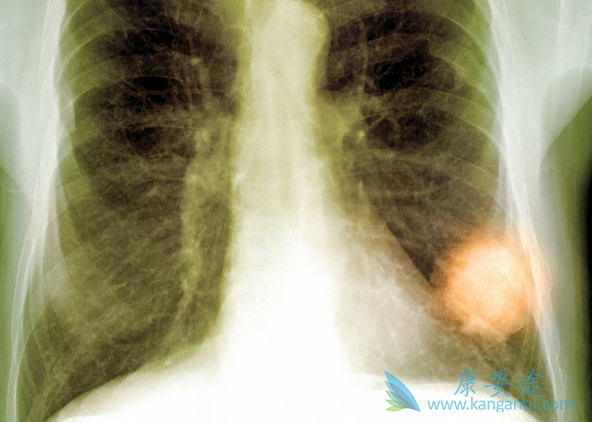

续孟加拉BEACON公司的Tagrix首款仿制奥希替尼上市后,孟加拉另一家大型药企Incepta公司也紧跟市场,迅速推出了世界上第一个瓶装奥希替尼仿制药Osicent,并把奥希替尼价格再次拉下一个平台!奥希替尼(Osicent)使用更方便,疗效有保证,价格亲民。

奥希替尼(Osicent)与Tagrix最大的不同就是瓶装的包装形式,Osicent保持了跟原研药一样的包装形式,一瓶30片,比盒装Tagrix的服用起来更加方便,运输也更加便利。从药物的有效成分来看,Osicent也保持了跟原研药一样的成分,每片含80mg奥希替尼(Osimertinib)。因此,它跟原研药的治疗效果是可以相媲美的。

从价格上来看,英国阿斯利康的原研药Tagrisso一个月费用为12750美元(约合87600人民币),而奥希替尼 Osicent是中国的肺癌患者可以负担的治疗方案。仿制药奥希替尼(Osicent)不但效果好,安全性也更好:使用一代EGFR抑制剂治疗非小细胞肺癌的有 44.8%的人曾出现≥3级(比较严重)的不良反应,有18.1%因此中止治疗;相比之下,使用奥希替尼的患者只有 33.7% 曾出现≥3级的不良反应,有 13.3% 中止治疗。